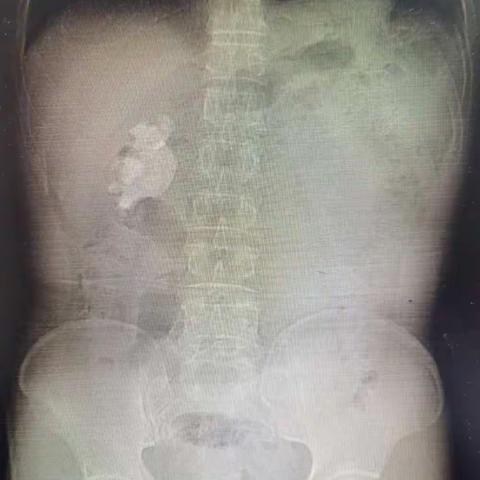

右侧经皮肾镜超声碎石取石术治疗右肾鹿角型结石